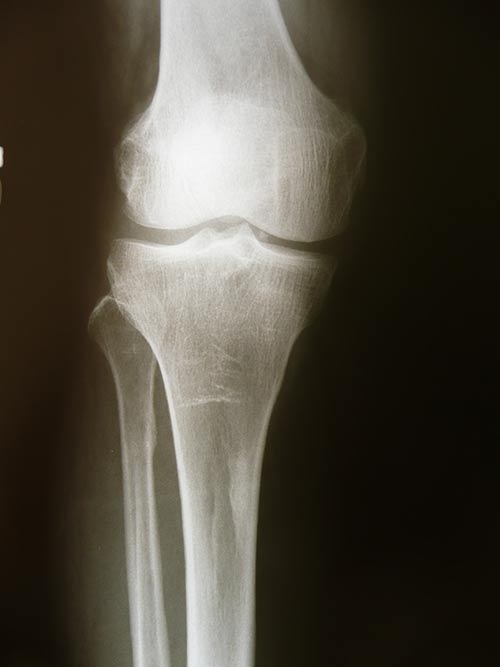

Rodilla del deportista o condromalacia de rótula

Este proceso refleja a menudo una anormalidad en el alineamiento de la rodilla, y se produce una lesión dolorosa de la superficie interna de la rótula a consecuencia del roce del cóndilo lateral del fémur. Es importante equilibrar las fuerzas que actúan sobre la rótula y la mantienen correctamente alineadas.